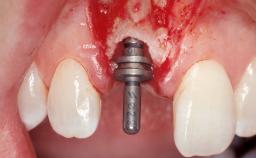

Late Flapless Placement of an Implant in a Maxillary Left Central Incisor Site

A 39-year-old male patient presented with a chief complaint of discomfort and gingival discoloration around his maxillary left central incisor. He was in good general health and was a non-smoker. His past dental history was significant because of the traumatic fracture of tooth 21 in a sporting accident at age 13. Initial dental treatment included endodontic therapy and a full-coverage restoration. The patient became symptomatic 5 years later, when structural failure of the tooth resulted in the dislodgment of the crown. Endodontic retreatment, apical surgery, and post-and-core restoration were performed.

Type of Implants One-Piece

Bone Augmentation Horizontal|Staged

Augmentation Materials Xenogenous|Membrane

Bone Volume Deficient horizontally, requiring prior grafting